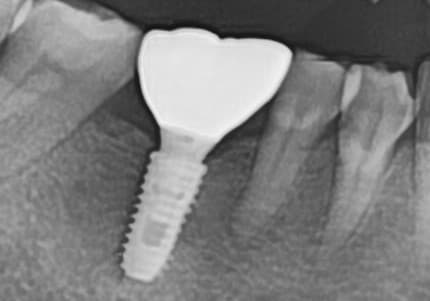

"뼈가 심하게 녹았는데

잇몸치료로 뼈가 차올랐어요"

심한 잇몸병으로 뼈가 많이 녹은 상태

잇몸치료와 뼈이식으로 뼈 재생 후 임플란트 성공